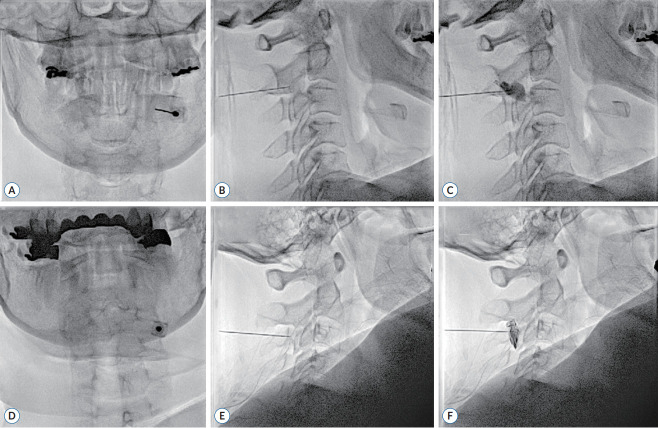

Objective: This study aimed to evaluate the clinical effects of medial branch blocks (MBBs) C2 and C3 in treating patients with medically intractable headaches.

Methods: The medical records of 81 patients with medically intractable headaches who underwent a C2/3 MBB between January 2019 and March 2022 were retrospectively reviewed. The degrees of pain were evaluated using a Visual analogue scale (VAS) score (rating 0-10) on baseline and after procedures. To evaluate patients' satisfaction for the treatment, self-reporting measurements were examined and were categorized as excellent (>90% pain relief), good (50-90% pain relief), fair (10-50% pain relief), and none (<10% pain relief).